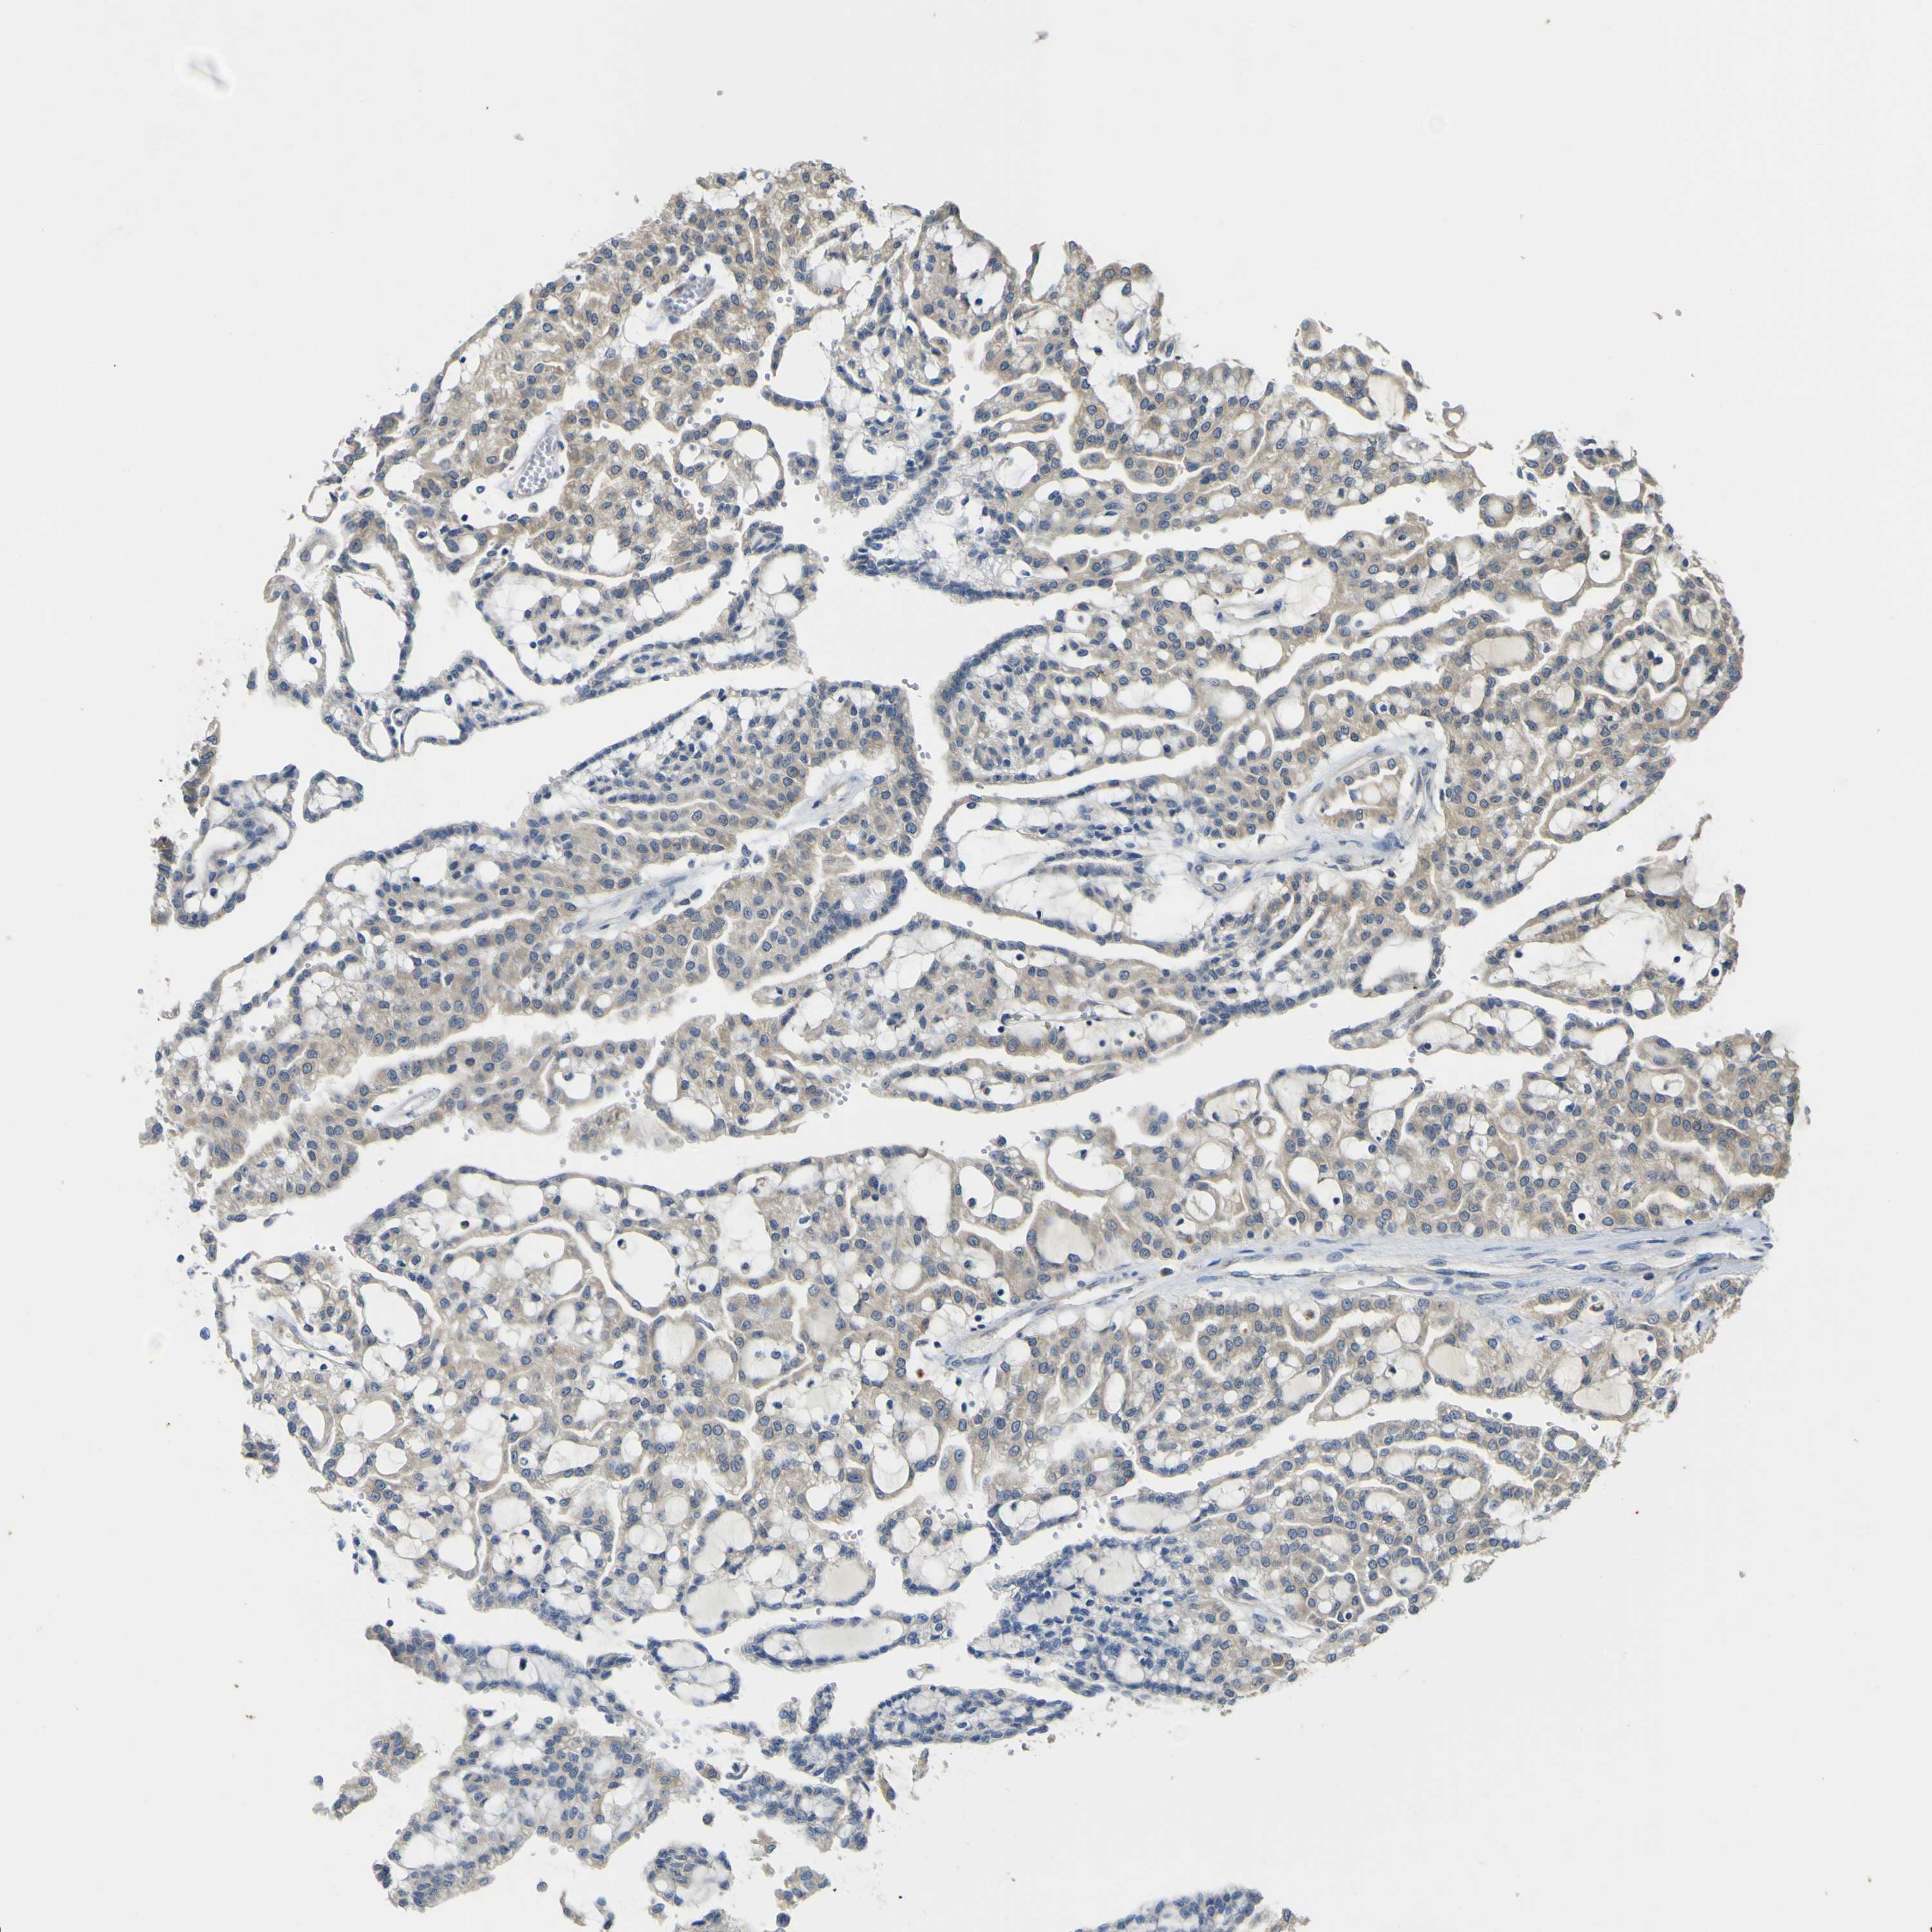

KIDNEY RENAL PAPILLARY CELL CARCINOMA (TCGA) - Interactive survival scatter ploti

The Survival Scatter plot shows the clinical status (i.e. dead or alive) for all individuals in the patient cohort, based on the same data that underlies the corresponding Kaplan-Meier plots. Patients that are alive at last time for follow-up are shown in blue and patients who have died during the study are shown in red.

The x-axis shows the expression levels (FPKM) of the investigated gene in the tumor tissue at the time of diagnosis. The y-axis shows the follow-up time after diagnosis (years). Both axes are complimented with kernel density curves demonstrating the data density over the axes. The top density plot shows the expression levels (FPKM) distribution among dead (red) and alive patients (blue). The right density plot shows the data density of the survived years of dead patients with high and low expression levels respectively, stratified using the cutoff indicated by the vertical dashed line through the Survival Scatter plot. This cutoff is automatically defined based on the FPKM cutoff that minimizes the p-score. The cutoff can be changed by dragging the vertical line or by entering a cutoff value in the square labeled "Current cut-off".

Under the Survival Scatter plot the p-score landscape (black curve; left axis) is shown together with dead median separation (red curve; right axis). Dead median separation is the difference in median mRNA expression between patients who have died with high and low expression, respectively. It is calculated as follows: median FPKM expression of dead patients with high expression - median FPKM expression of dead patients with low expression. This is intended to aid the user in visually exploring custom cutoffs and the associated p-scores and dead median separation.

Individual patient data is displayed and can be filtered by clicking on one or more of the category buttons on the top of the page. Categories describing expression level and patient information include: high, low, alive, dead, female, male and tumor stages. The scale of the x-axis can be toggled between linear and log-scale by clicking on the "x log" button. Mouse-over function shows TCGA ID, patient information and mRNA expression (FPKM) for each patient.

& Survival analysisi

Kaplan-Meier plots summarize results from analysis of correlation between mRNA expression level and patient survival. Patients were divided based on level of expression into one of the two groups "low" (under cut off) or "high" (over cut off). X-axis shows time for survival (years) and y-axis shows the probability of survival, where 1.0 corresponds to 100 percent.

LDLR is not prognostic in Kidney Renal Papillary Cell Carcinoma (TCGA)

Best expression cut offi

Based on the FPKM value of each gene, patients were classified into two groups and association between prognosis (survival) and gene expression (FPKM) was examined. The best expression cut-off refers the FPKM value that yields maximal difference with regard to survival between the two groups at the lowest log-rank P-value. Best expression cut-off was selected based on survival analysis .

When clicking on this number, the vertical dashed line indicating cut-off, the interactive survival plot, and the Kaplan-Meier curve will be adjusted to show results based on the best expression cut-off.

: 0.71